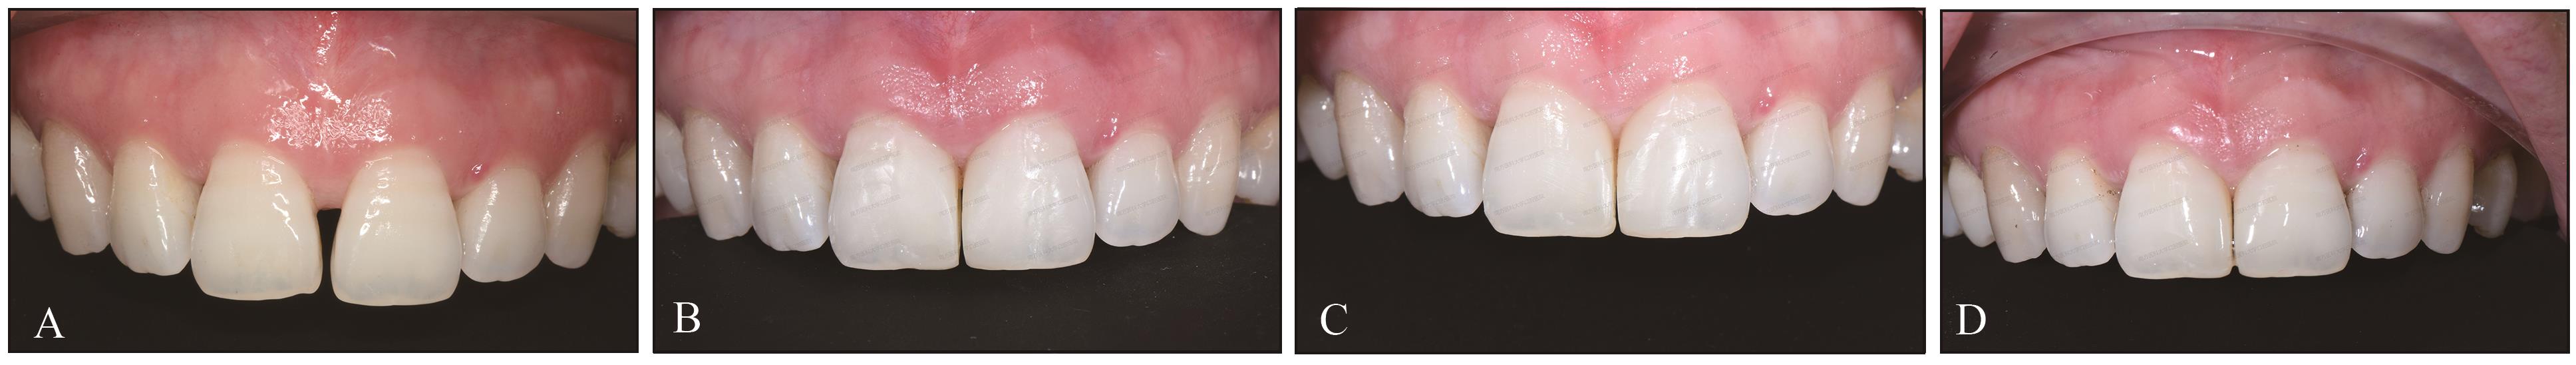

中切牙间隙和龈乳头变化A:术前;B:术后即刻;C:术后1周;D:术后1年。"